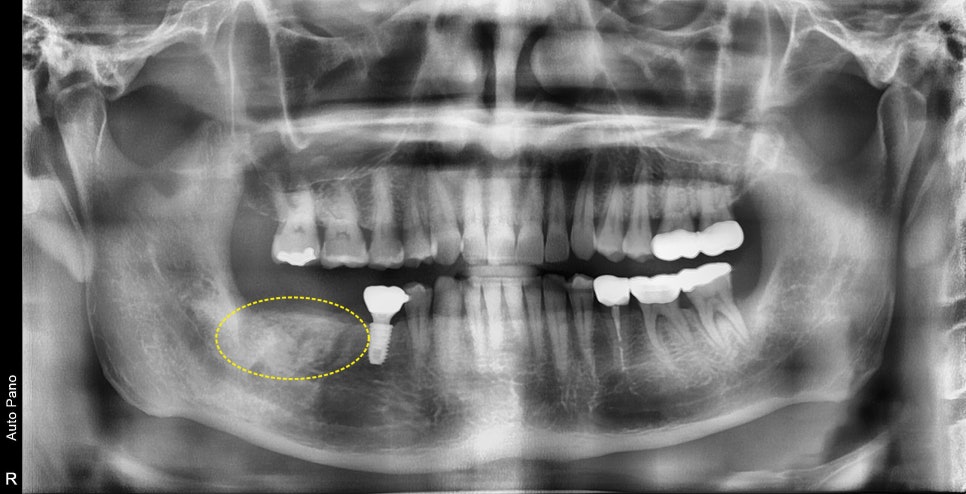

예를 들어

이렇게 사진상 진단시는 발치와 동시에 임플란트 수술이

가능했지만 제때 치료 시기를 놓치게 되면

시간이 지나 주변 뼈들이 염증에 의해 더 녹아

발치 후 치조골이식을 진행한 후

회복후 수술이 필요한 경우도 있습니다

노란 원으로 표시된곳이 치조골이식후 회복된상태입니다

물론 결과적으로 치료가 잘 마무리가 되지만

치료시기를 놓치게 되면 치료기간이 2배로 늘어날수 있습니다.